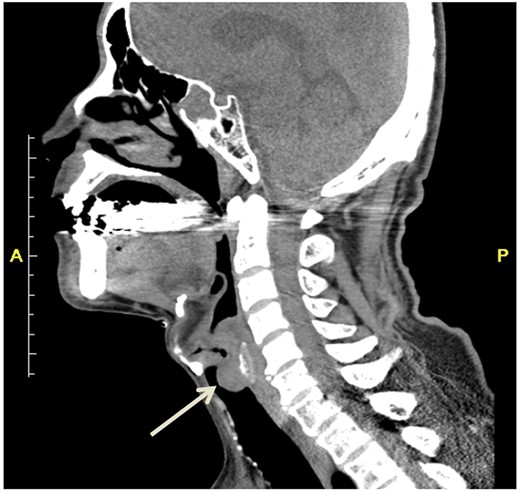

Upon arrival, he complained of severe dyspnea with inspiratory stridor in his throat. Computed tomography revealed a mass arising from the posterior wall of the trachea (Fig. 1). Bronchoscopy revealed a white subglottic tumor occupying 80% of the tracheal diameter (Fig. 2). We performed an emergency tracheostomy under topical anesthesia, and the symptoms improved dramatically. For 5 days after the tracheostomy, hydrocortisone was prescribed; however, no tendency toward reduction of the mass could be identified during follow-up bronchoscopy. To shorten the treatment period, we performed a resection of the tumor under bronchoscopy 6 days after the tracheostomy.

Computed tomography revealed a mass arising from the posterior wall of the trachea (arrow).